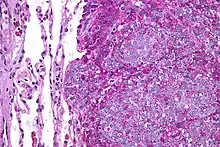

| Micrograph of metastatic Ewing sarcoma (right of image) in normal lung (left of image). PAS stain. | |

Ewing sarcoma is a small-blue-round-cell tumor that typically has a clear cytoplasm on H&E staining, due to glycogen. The presence of the glycogen can be demonstrated with positive PAS staining and negative PAS diastase staining. The characteristic immunostain is CD99, which diffusely marks the cell membrane. However, as CD99 is not specific for Ewing sarcoma, several auxiliary immunohistochemical markers can be employed to support the histological diagnosis.[23] Morphologic and immunohistochemical findings are corroborated with an associated chromosomal translocation, of which several occur. The most common translocation, present in about 90% of Ewing sarcoma cases, is t(11;22)(q24;q12),[24][25] which generates an aberrant transcription factor through fusion of the EWSR1 gene with the FLI1 gene.[26]